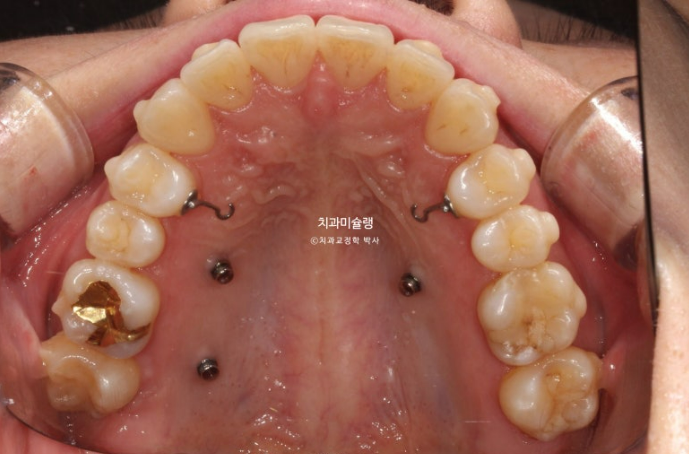

두번째 세트 장치는 총 33개가 나왔으며 24년 9월부터 25년 4월까지 꼈습니다.

교정용 나사도 추가로 심고 뺏다꼈다 하는 고무줄 처방도 들어갔습니다.

25년 4월, 두번째 세트 장치를 모두 낀 후 모습입니다.